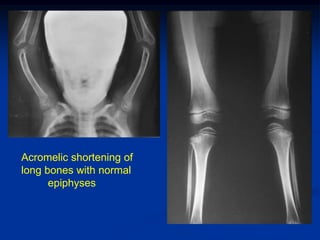

Case #1         Ellis VanCreveld Syndrome

Acromelic dwarfism in a young girl with polydactylism

Acromelic shortening of

long bones with normal

epiphyses